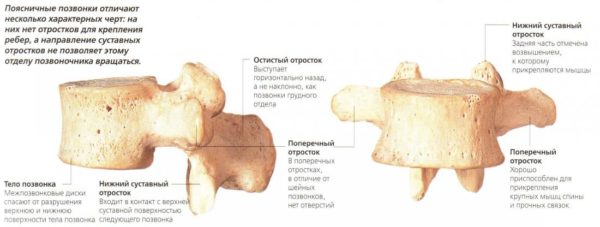

Поясничные позвонки

Каждый позвонок имеет строго цилиндрическое строение. В качестве фрагмента опорной нагрузки держит форму полукольца или дуги, от которой уходят в стороны отростки. На дугах расположены отверстия, образующие сквозной канал вдоль всего хребта. В этом канале проходят сосуды, нервы и сосредоточен позвоночный мозг.

Тело поясничного позвонка больше в ширину, чем спереди назад. Ширина больше высоты.

От тела позвонка назад идёт дуга, замыкающая позвоночное отверстие и переходящая далее в остистый отросток. На плоскости дуги в обе стороны расположены поперечные отростки, которые являются рудиментами рёбер. У основания поперечных отростков поясничных позвонков заметен рудимент истинных поперечных отростков (processus accessorius), который при большой длине (4 мм) приобретает форму шила (processus styloideus). Авторы М. Г. Привес, Н. К. Лысенков, В. И. Бушкович замечают, что его не следует принимать за патологическое образование. На верхней и нижней гранях дуги расположены парные верхние и нижние суставные отростки. В четырёх верхних поясничных позвонках остистые отростки направлены прямо назад, суставные расположены сагиттально. Позвоночные отверстия, начиная со второго поясничного позвонка, постепенно сужаются, что связано с анатомией спинного мозга.

Тело пятого поясничного позвонка в направлении к остистому отростку имеет клиновидную форму, при этом оно наклонено вперед, так как крестцовая кость направлена назад, формируя кифоз. Суставные отростки размещены в полуфронтальной, полусагиттальной плоскостях.